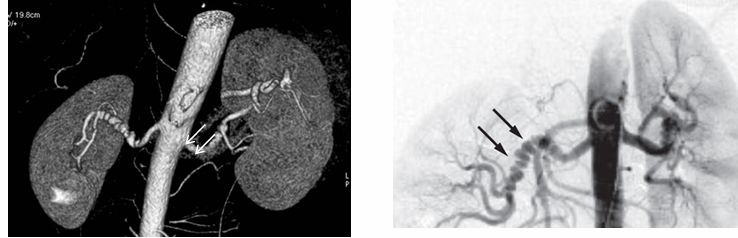

-”string of beads” characteristic of medial fibromuscular dysplasia

-renal artery stenosis

renovascular hypertension

-diagnosis: renin levels can be high but normal levels do not rule out renal artery stenosis

-imaging studies: sonography with duplex doppler, magnetic resonance angiography, CT angiography, angiography

-due to fibromuscular dysplasia in young individuals- treat with angioplasty

-due to atherosclerotic disease in older individuals with CV risk factors: suspect with pre-existing peripheral vascular disease or long history of smoking, recurrent flash pulmonary edema, treatment with angioplasty + stent placement